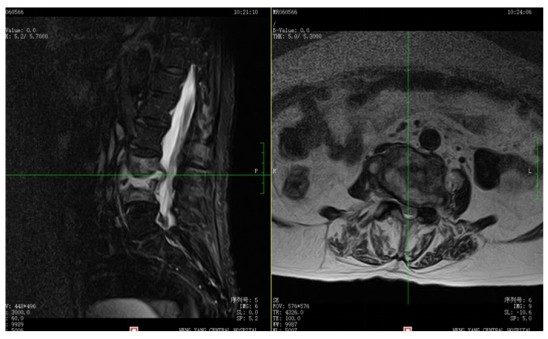

為解決老人病痛,脊柱外科錢軍博士團(tuán)隊(duì)對(duì)其進(jìn)行了詳細(xì)的查體以及全面細(xì)致的評(píng)估,診斷為L3、4脊柱結(jié)核伴病理性骨折、椎旁膿腫,患者腰部疼痛癥狀逐漸加重,病灶已經(jīng)壓迫神經(jīng)引起了截癱。